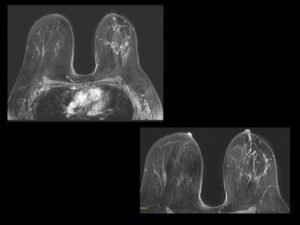

1. Irregular mass with spiculations and microcalcifications in supra-areolar region of left breast – BIRADS 5. 2. On MRI – Irregular enhancing mass with surrounding extensive clumped and nodular enhancement in ductal distribution in upper quadrant- representing multifocal DCIS or extensive ductal spread. 3. Thickening in left axillary lymph nodes- likely metastaticCortical

1. Invasive ductal carcinoma with multifocal DCIS / extensive intraductal spread. 2. MRI changes the management from Breast conserving surgery to MRM because of extensive intraductal component other then mass.